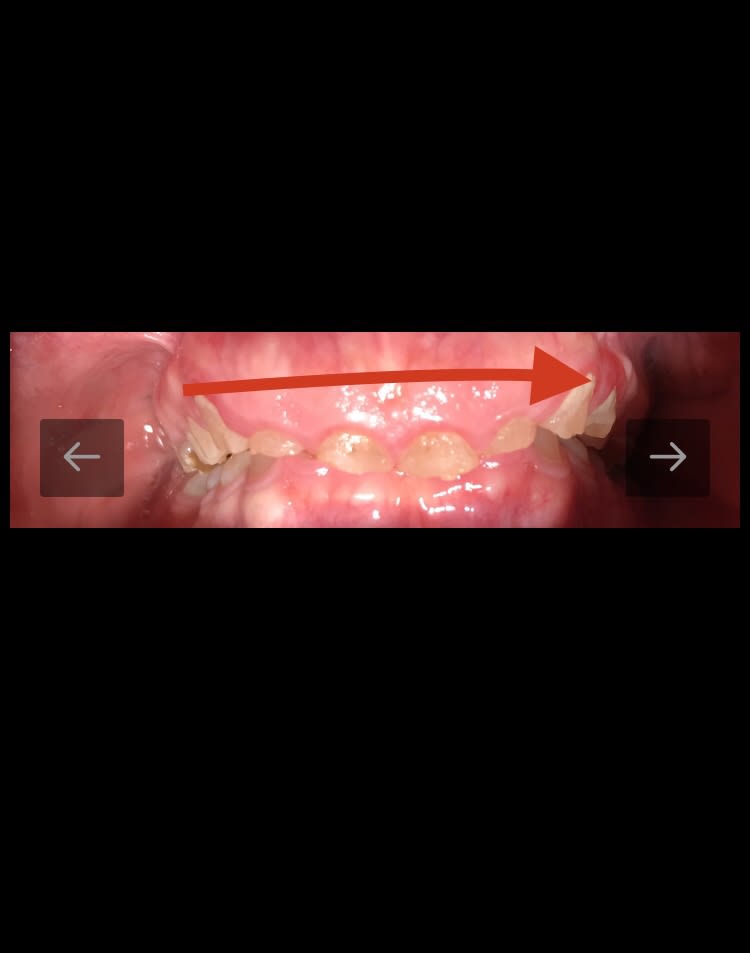

Non il n’ y a pas eu de traitement ortho. Et le patient m’a dit qu’il y avait ce même problème de fragilité dentaire chez d’autres membres de sa famille.

Je ne vois pas comment on pourrait faire une élongation dans ce genre de cas .... et aligner les incisives avec les canines. Il y a bien 1,5 /2 cm de dénivelé entre le collet des canines et le collet des incisives :)

Est ce que tous le monde serait d'accord de commencer par un traitement ODF histoire de corriger les malpositions, les égressions et de libérer l'espace prothétique en antérieur ?

Après élongations coronaires si nécessaires et couronnes en antérieur et sur les 6 ?

C’est un patient qui a 24 ans . Je vais le revoir pour les radios.

Pour répondre à Prunelles , sa demande est esthétique. Il vient à la base pour le secteur antérieur. Mais il a compris qu’il faudra faire plus que le secteur antérieur.

Bon, même si on n'aura jamais la réponse because patient, je me pose vraiment la question de l'étiologie.

24 piges, même le pire des bruxos ne fusille pas ses dents comme ça en quelques années.

L'hygiène inexistante n'a aucune incidence ici.

Les usures sont largement concentrées en antérieur, en postérieur on n'a quasiment rien. Hormis sur les dents sans antagonistes, probablement parce qu'elle viennent buter dans les mouvements.

Je soupçonne très fort une attaque acide.

Je maîtrise mal les différents prod illégaux, de mémoire les amphets ça fait un peu ce genre de chose, +bruxisme.

Ou un produit en utilisation pro, vapeurs acides de je ne sais quoi.